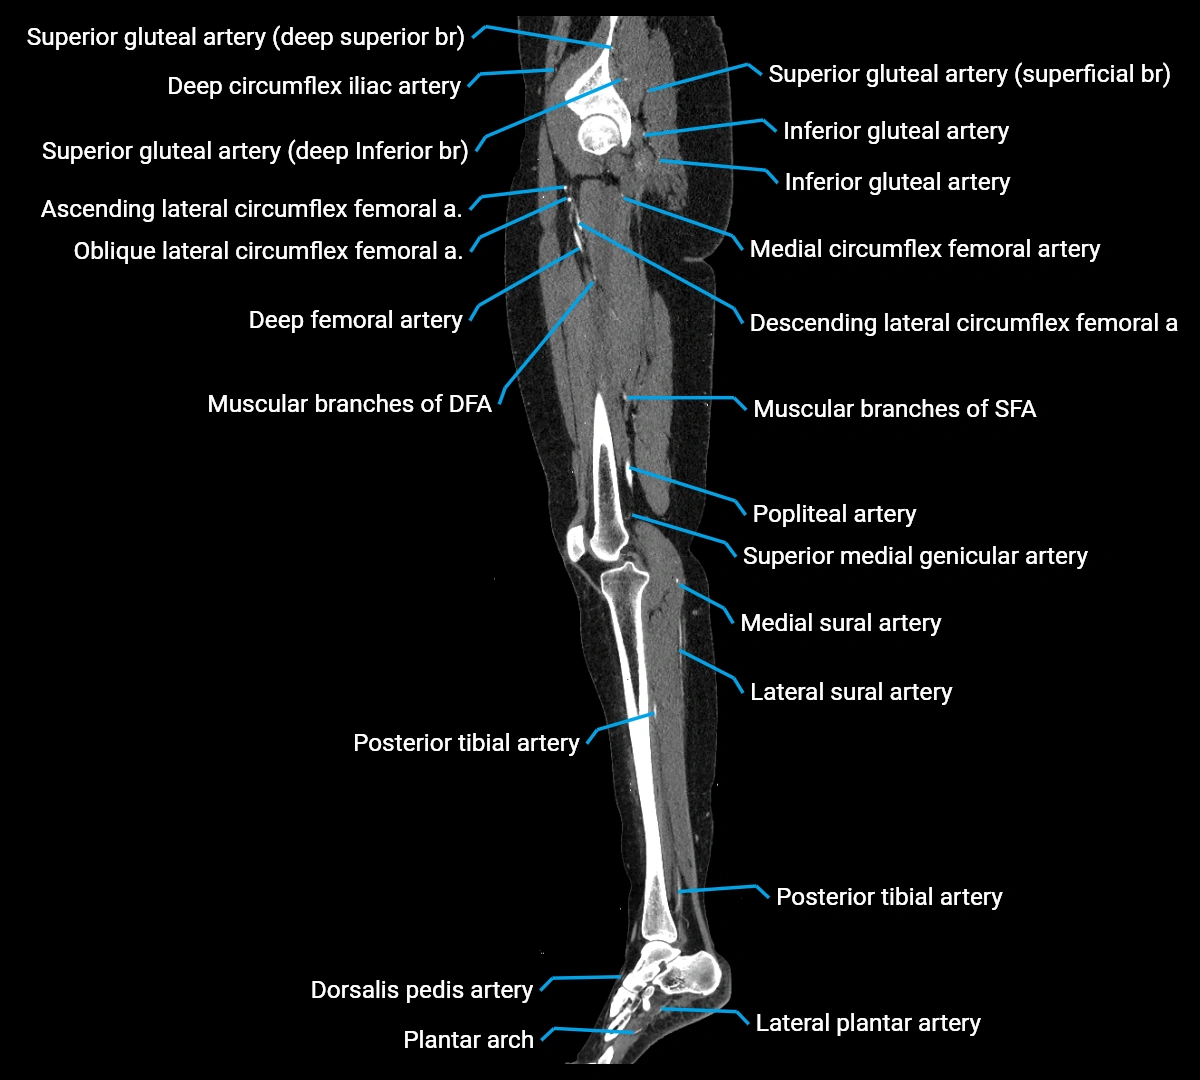

CT images

image